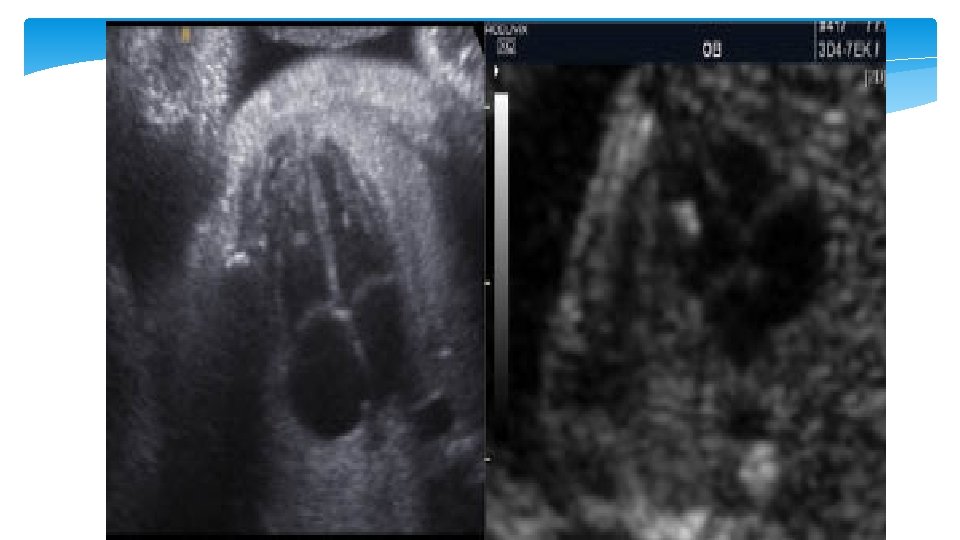

Single umibical artery Is the most common anomaly of the cord and occurs in approximately 1% of all deliveries. It may result from primary aplasia of one of the two umbilical arteries or as a consequence of atrophy of one artery. It is more commen in the left artery and occurs more often in twin gestation. It is sometimes accompanied with abnormal cord insertion in the placenta, i. e. marginal and velamentous cord insertions

Single umbilical artery single umbilical artery (SUA) and an increased risk of aneuploidy when additional fetal malformations are detected. The rate of aneuploidy with isolated SUA is not known, but most experts do not recommend routine chromosomal analysis if there are no other malformations or other indications for genetic amniocentesis.